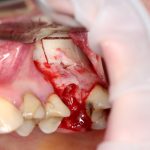

Для получения костного блока, мы открываем донорскую зону, наружную косую линию нижней челюсти.

Получение костного аутотрансплантата.

Здесь потребуется пародонтологический зонд с миллиметровой разметкой или какой-то другой измерительный прибор (операционная линейка). Ранее по КЛКТ я измерил костный дефект, теперь нужно нанести границы будущего костного блока на донорскую зону.

Для получения костного блока мы использовали ультразвуковую пьезохирургическую систему. Это самый удобный и безопасный инструмент для проведения подобных манипуляций. С помощью него мы сформировали и выделили костный блок. Он должен отделяться легким движением остеотома или элеватора. Как это сделать правильно — читай здесь>>